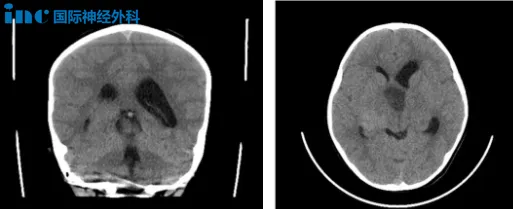

8岁男性患儿小康确诊为视神经-下丘脑胶质瘤,肿瘤侵犯视神经、视交叉、视束、视放射、丘脑底垂体轴、第三脑室和脑底动脉环等重要结构。临床表现包括视力下降、头痛和呕吐等症状。

面对该病例,多数医生建议采取保守放化疗方案。但肿瘤持续增大会导致双目失明风险,手术关键难点在于如何安全分离肿瘤并最大限度保留视神经功能。经与巴特朗菲教授远程咨询后,最终选择手术治疗方案。

手术切除率预计达80%,仅双侧失明患儿可获得90%以上切除率。巴特朗菲教授主刀实施次全切除手术,成功切除巨大视路胶质瘤,仅神经表面残留少量肿瘤组织。

术后第二天患儿转出ICU,未出现脑水肿、脑出血、呼吸障碍及内分泌功能紊乱等常见并发症。原有视力得到保留,无新发神经功能损伤,术后恢复状况良好。